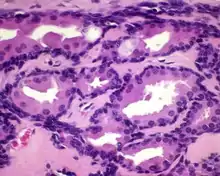

All of the tumors are unencapsulated, but are usually well defined or circumscribed. The overlying surface epithelium is not involved. The tumor shows a dual or biphasic appearance, with glandular or cystic spaces showing inner luminal secretory cells with abundant granular, eosinophilic cytoplasm subtended by basal, myoepithelial cells at the periphery, adjacent to the basement membrane. The luminal cells will often have decapitation (apocrine) secretions and will also have yellow-brown, ceroid, lipofuscin-like (cerumen) pigment granules. There is no pleomorphic, limited mitoses, and no necrosis.[2]